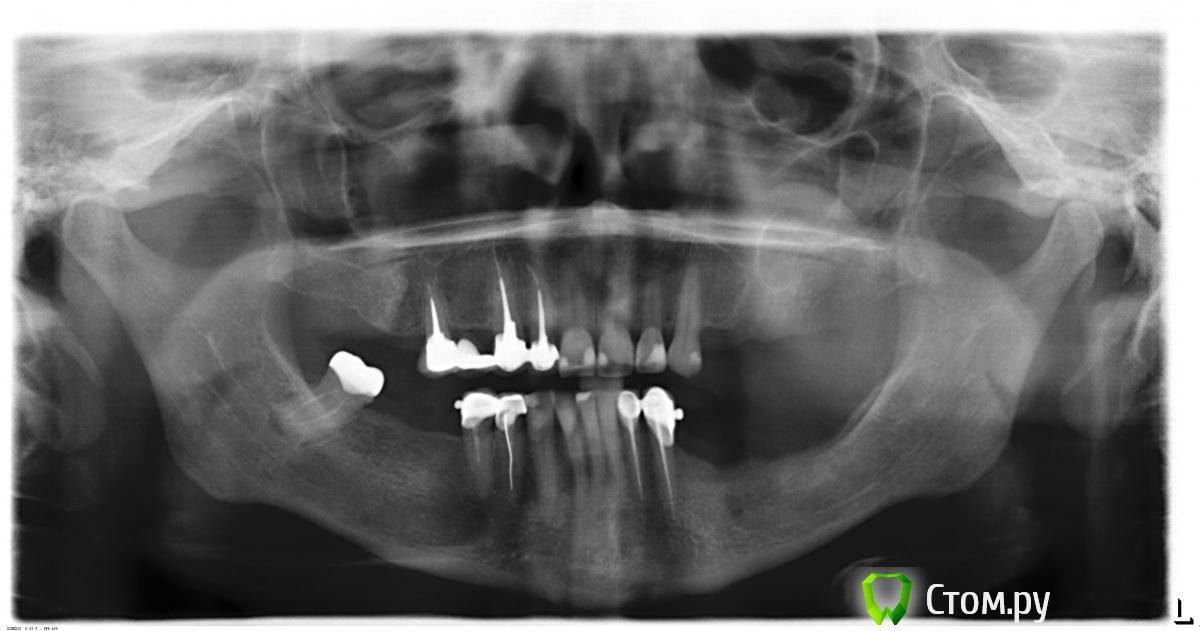

Tatiana54 Опубликовано 23 ноября, 2014 Поделиться Опубликовано 23 ноября, 2014 (изменено) Здравствуйте! Я постоянно проживаю в г. Петропавловске-Камчатском и т.к. выбор специалистов у нас невелик, то решилась провести все работы в Москве или, если не удастся найти специалиста по рекомендации, в Санкт-Петербурге, даже если придется лететь несколько раз. Объем работ в моем случае большой и принимать поспешных решений мне не хотелось бы. Поэтому обращаюсь к вам. У меня было несколько консультаций после которых мне было рекомендовано:- удаление 8-ки;- лечение корней некоторых зубов верхних и нижних челюстей, т.к. там есть проблемы;- установка 7 имлантантов Nobel на 16, 24, 26, 34, 36, 37, 46, плюс 3 имплантанта на 7ки для более эффекивного пережовывания пищи;- установку отдельной коронки на имплантат 16, мостовидный протез на 24-25 (подвесной)-26; второй мостовидный протез 34-35 (подвесной) -36-37; отдельная коронка 46. Итого - 10 имплантатов и 12 зубов.- возможно, понадобится костная пластика, а также пластика десны. Так как не было на руках трехмерного снимка, то окончательная необходимость этого мероприятия еще не подвердилась;- установка временных коронок после приживания имплантантов для формирования десны и адаптации к жеванию после длительного отсутствия зубов, но это не обязательно;- установка циркониевых коронок. В плане цены, то здесь у меня на сегодня главный вопрос, в какую сумму мне может обойтись имплантация при условии, что будут:- устанавливаться имплантанты Nobel или аналоги соответствующего качества;- выполнена пластика кости и десны;- устанавливаться временные коронки;- устанавливаться циркониевые коронки;- устанавливаться циркониевые коронки на передние ряды зубов (верх и низ)? Разброс цен в Москве и СПб настолько значителен, что даже теряюсь.В Москве мне озвучили сумму близку к 2 млн, без учета стоимости пластики кости и десны, т.к. сказали, что не надо делать, и без учета стоимости коронок на передние ряды зубов. Одни только временные коронки они насчитали на 150 т.р.В СПб, по моим расчетам, просто имплантация без пластики кости (десны) и без коронок на передние ряды зубов обойдется мне в районе 1 млн. Суммарно вопросы следующие: 1. Если вам что добавить к плану лечения во втором абзаце? 2. Действительно ли имплантанты Nobel самые лучшие в своем роде и их установка возможна, в ряде случаев, без проведения пластики кости? Если нет, то на что обратить мне внимание? 3. Можно ли обойтись без платики кости? По запросу могу скинуть ссылку на 3D снимок обеих челюстей. 4. Можно ли установить все необходимое количество имплантантов за один визит и сколько это займет времени? 4.1. Можно ли будет также установить циркониевые коронки на передние ряды зубов во время или сразу после установки имплантантов? Понятно, что предварительно передния ряды зубов буду пролечены, а коронки буду заранее изготовлены. 4.2. Если основной этап имплантации займет более 3 часов, то можно ли его провести под общим наркозом, учитывая, что мне уже 60 лет или лучше добавить к обычному наркозу "сидацию"? В чем ее преимущества, насколько безопасна? 4. Какой минимальный и макисмальный бюджет мне закладывать в решение моих зубных проблем при озвученных в третьем-четвертом абзацах условиях? Дополнительно интересует возможность удаления всех зубов и моментальной установки имплантантов под нагрузкой. Возможно ли такое и насколько целесообразно в моем случае? Спасибо за ваши комментарии. Снимок сделан 25.10.2014. Изменено 23 ноября, 2014 пользователем Tatiana54 Ссылка на комментарий

SDC Опубликовано 24 ноября, 2014 Поделиться Опубликовано 24 ноября, 2014 (изменено) Суммарно вопросы следующие: 1. Если вам что добавить к плану лечения во втором абзаце? 2. Действительно ли имплантанты Nobel самые лучшие в своем роде и их установка возможна, в ряде случаев, без проведения пластики кости? Если нет, то на что обратить мне внимание? 3. Можно ли обойтись без платики кости? По запросу могу скинуть ссылку на 3D снимок обеих челюстей. 4. Можно ли установить все необходимое количество имплантантов за один визит и сколько это займет времени? 4.1. Можно ли будет также установить циркониевые коронки на передние ряды зубов во время или сразу после установки имплантантов? Понятно, что предварительно передния ряды зубов буду пролечены, а коронки буду заранее изготовлены. 4.2. Если основной этап имплантации займет более 3 часов, то можно ли его провести под общим наркозом, учитывая, что мне уже 60 лет или лучше добавить к обычному наркозу "сидацию"? В чем ее преимущества, насколько безопасна? 4. Какой минимальный и макисмальный бюджет мне закладывать в решение моих зубных проблем при озвученных в третьем-четвертом абзацах условиях? Дополнительно интересует возможность удаления всех зубов и моментальной установки имплантантов под нагрузкой. Возможно ли такое и насколько целесообразно в моем случае? 1. Костная аугментация и аугментация десны должны быть в плане. В Вашем случае значительная атрофия костной ткани в 3 квадранте по вертикали и я думаю, что без направленной костной регенерации не обойтись.2. У Нобеля много моделей имплантатов. Есть - ничего, а есть - так себе. Узнайте у Д-ра, какая модель Нобеля планируется для имплантации.3. КТ грузите на файлообменник и постите ссылку.4. Можно за 1 визит, в том случае, если размеры костной ткани по ширине и высоте будут соответствующие для имплантации. По времени: 1-2 часа. По ОПТГ не ясно, нужен ли синус-лифтинг, нужно КТ.4.1. Нельзя. Конечно понятно, что Вам желательно "ВСЕ за 1 визит" и максимально сократить количество приемов/приездов/, но хирургия и постоянное протезирование в 1 визит - это 10 шагов навстречу к переделке всей протетики.4.2. Имплантация и костная пластика под седацией - оптимальный вариант в Вашем случае. Можно и без нее или под наркозом - Вам выбирать.Как определитесь с исполнителем, про бюджет вопрос к нему. Не забудьте заложить транспортные расходы, которые составят ~1/3 -1/2 бюджета. Если основная цель - качество, то было бы правильно сделать выбор клиники, соответствующий ожиданиям и поставленной задаче в разных городах, сравнить планы лечения, выяснить, почему одни считают, что без аугментации возможно, а другие указывают на необходимость ее.По результатам: искать исполнителя с планом, схожим и близким к оптимальному, озвученному и аргументированному в городе N.И даже в этом случае сравнение стоимости не будет корректным. Изменено 24 ноября, 2014 пользователем SDC 1 Ссылка на комментарий